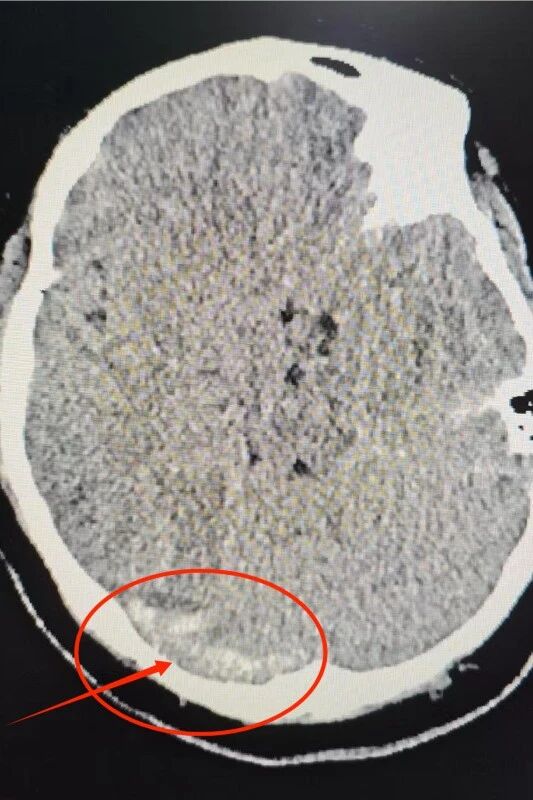

11 月 6 日凌晨,阿女士头痛突然加剧,随即出现言语不清、右侧肢体无力和呕吐等典型神经系统症状。当地县医院头颅 CT 提示脑出血后立即建议转至我院进一步救治。然而在 120 转运途中,阿女士病情急剧恶化,出现意识障碍、全身抽搐、血氧持续下降,生命一度危在旦夕。

阿女士到达我院后,急诊团队迅速开展气管插管、呼吸机辅助通气、抗癫痫及镇静等紧急处置。经进一步影像检查,卒中团队明确诊断为颅内静脉窦非脓性血栓形成,伴症状性癫痫及脑出血,是一种危险性极高、进展迅速的急危重症。援疆专家、神经内科主任林镇洲在评估后立即作出决定:必须紧急取栓,尽快恢复颅内静脉回流,才能最大限度保护患者生命和脑功能。